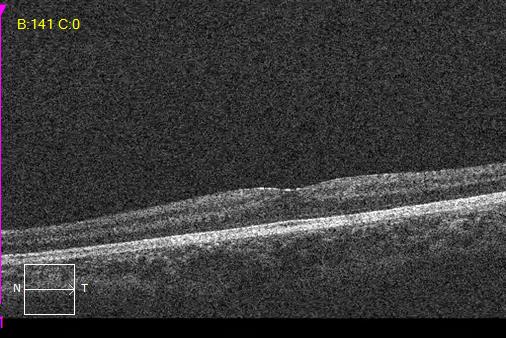

Macular OCT scans and optic nerve head analysis show thin RNFL in both eyes.